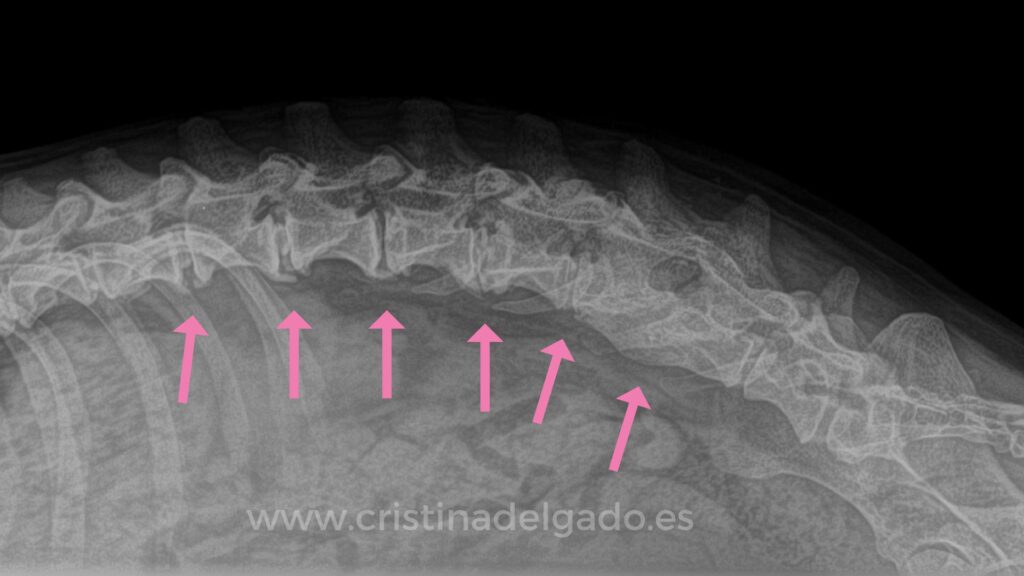

Diagnóstico Preciso: Más Allá de una Radiografía

Si se sospecha una hernia discal, el veterinario realizará un examen físico y neurológico detallado. Para confirmar el diagnóstico y determinar la ubicación y gravedad exactas de la compresión, se necesitan técnicas de imagen avanzadas. Una radiografía simple no suele ser suficiente para visualizar el disco herniado y la médula espinal con el detalle necesario.

• Mielografía: Se inyecta un medio de contraste en el canal espinal y se toman radiografías. El contraste resalta la médula espinal, permitiendo ver dónde está siendo comprimida.